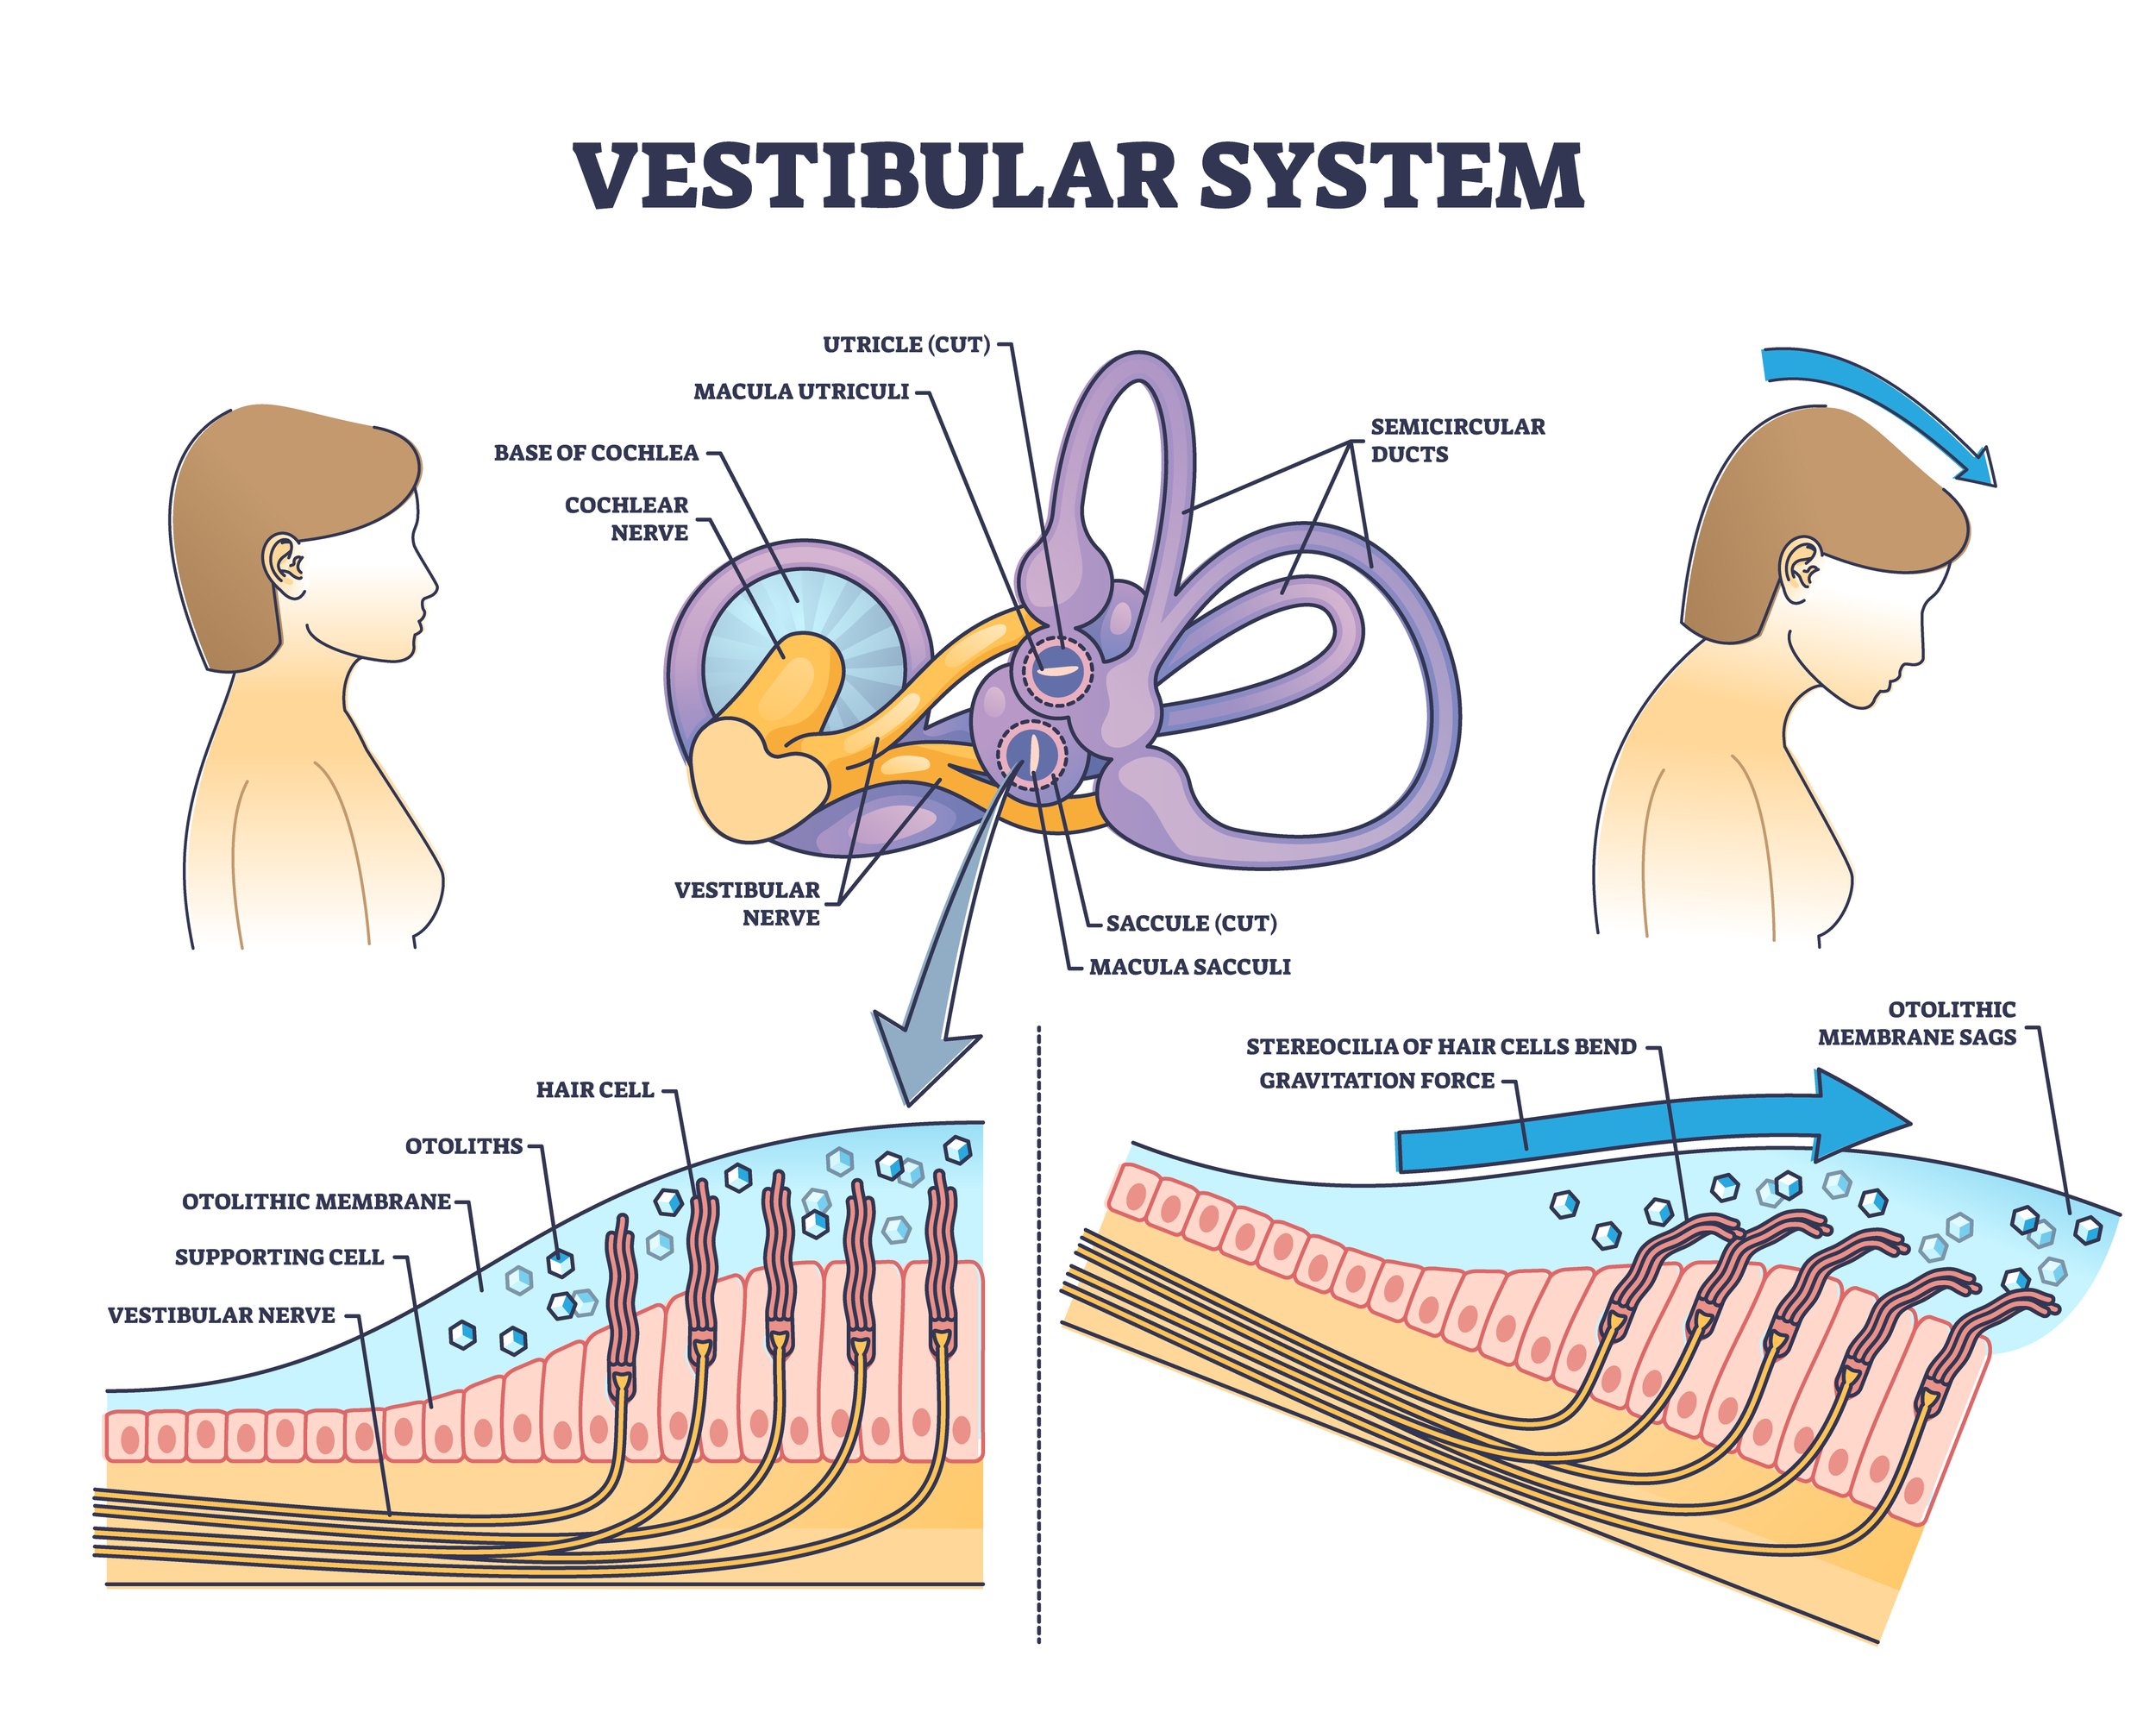

- Inner Ear (Vestibular System): Our ears have small parts that feel when we move. There is liquid inside that moves slower than our heads when we turn or tilt. The slow-moving liquid pushes on tiny hairs, which then tell our brain if our head is moving and how.

Our brain uses the information from our inner ear to help control our muscles and even our eyes…

So we can stay balanced and see clearly even when we're moving.

All these parts – our eyes, inner ear, and body nerves – work together to help us stand up straight and not fall over.